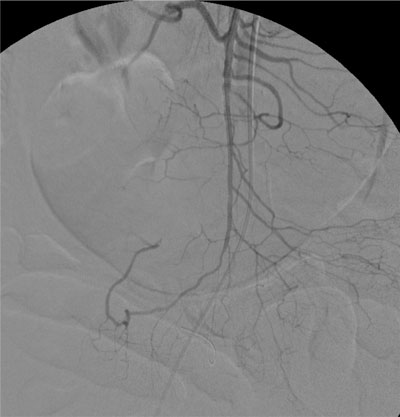

Paciente de 84 anos, sexo feminino, hipertensa, portadora de fibrilação atrial crônica e marcapasso definitivo associado a insuficiência coronariana. Procurou atendimento por apresentar forte dor abdominal em cólica, iniciada há poucas horas e que não cessou com uso de analgésicos tradicionais. Ao exame físico, observou-se ritmo cardíaco irregular por fibrilação atrial crônica e dor abdominal difusa à palpação profunda, sem sinais de descompressão dolorosa do abdome. Indicado estudo angiográfico realizado cerca de 3 horas do inicio da dor, que demonstrou oclusão do terço médio da artéria mesentérica superior. Realizado tratamento endovascular, mediante trombólise mecânica associada ao implante de stent em estenose localizada no terço médio da artéria mesentérica superior, sem intercorrências. Paciente permaneceu internada em Unidade de Terapia Intensiva, encontrando-se hemodinamicamente estável no primeiro dia após o procedimento. Entretanto, como os padrões laboratoriais de acidose metabólica e leucocitose com desvio à esquerda permanecessem, foi submetida à laparotomia exploradora sendo encontrado segmento cianótico, sendo optado preventivamente por ressecção de 70 cm de intestino delgado à 2m do ângulo de Treitz sem intercorrências. Após melhora dos padrões clínicos e laboratoriais, recebeu alta da UTI, permanecendo internada no mesmo Hospital. No 10 dia pós operatório a paciente apresentava desconforto abdominal, sendo realizado nova arteriografia que mostrava a perviedade da artéria mesentérica superior. No trigésimo dia pós operatório a paciente se alimentava e apresentava evacuações normalmente mas mantinha desconforto abdominal e leucocitose. Foi submetida a uma nova laparotomia sem achados de isquemia ou de infecção na cavidade.